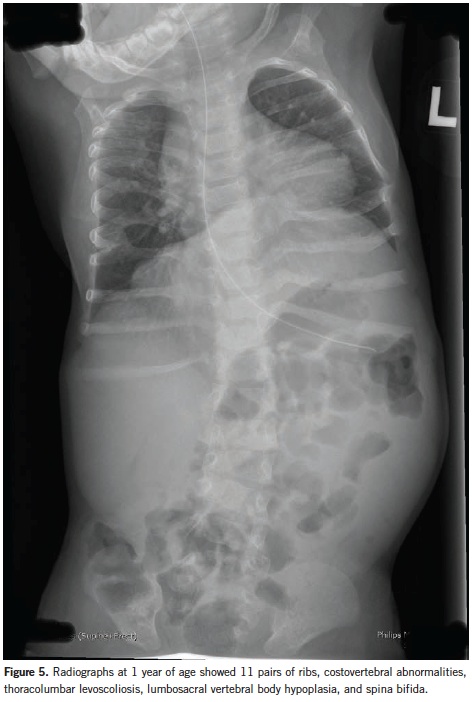

At 1 year of age, chest and abdominal radiographs showed dysmorphic ribs, 11 pairs of ribs, spina bifida (from the 12th thoracic vertebrae to the sacrum), levoscoliosis of approximately 27° (from the 8th thoracic to the 5th lumbar vertebrae), and decreased anteroposterior diameter of the lumbosacral vertebral bodies (Figure 5).